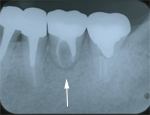

5.2年後

根尖部の黒い影が、消えないので、

長い間仮歯のまま様子を見ていましたが、

ようやくクラウンをかぶせ、完成させました。 |

6.20年後

20年経ちました。

本人はなんら違和感を感じないそうです。 |

根管治療後、根尖部の影がなかなか消えないので不安があった症例でしたが、

その後, 問題もなく、20年経過しました。